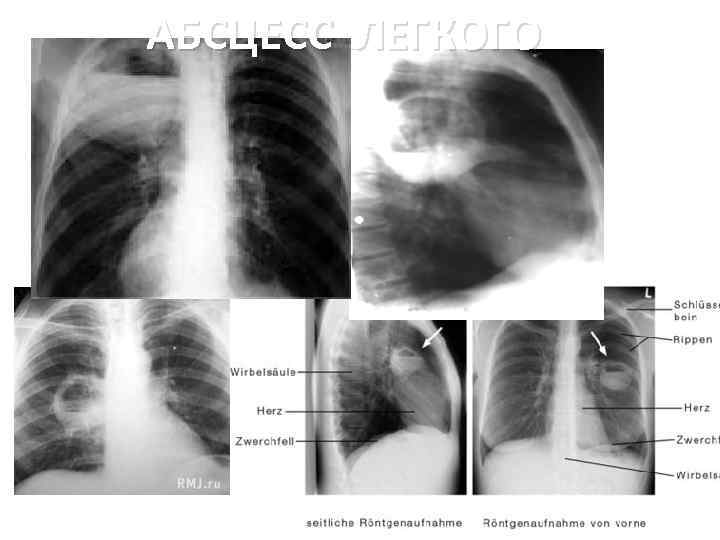

Рентгенологическая ДИАГНОСТИКА АБСЦЕССА ЛЕГКОГО П П П Краткие учебные материалы для подготовки к занятиям. © Романова Екатерина Игоревна, ассистент кафедры пропедевтики внутренних болезней и гигиены, 2014

АБСЦЕСС ЛЕГКОГО